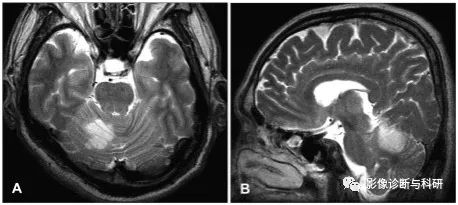

53 岁,男子,眩晕、恶心和呕吐。MR提示小脑后下动脉 (PICA) 分布区高信号,邻近的脑干和第四脑室受到压迫。